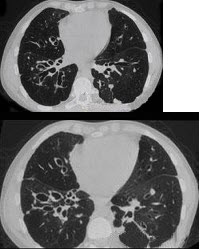

193、单项选择题

女,28岁,反复咯血半月余,CT检查如图,选出最可能的诊断()

A.肺结核

B.肺癌

C.间质性肺炎

D.支气管扩张

E.肺脓肿